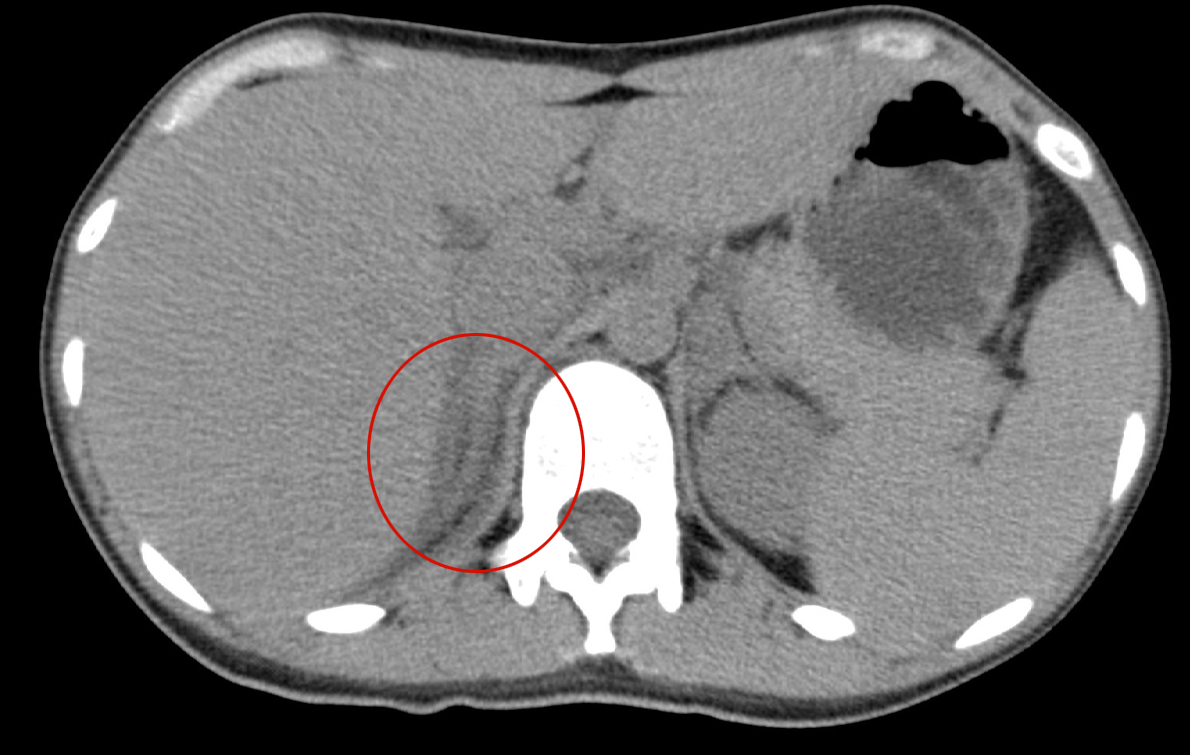

No.12420歳代 女性

- 【KEY画像】

- 左副腎の腫大

- 左副腎の造影不良

- 脾腫

- 腋窩リンパ節腫大